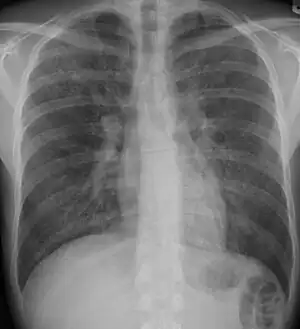

-

Chest radiograph showing interstitial lung disease -

Chest radiography is usually the first test to detect interstitial lung diseases, but the chest radiograph can be normal in up to 10% of patients, especially early in the disease process.[17][18]

High-resolution CT of the chest is the preferred modality and differs from routine CT of the chest. Conventional (regular) CT chest examines 7–10 mm slices obtained at 10 mm intervals; high resolution CT examines 1–1.5 mm slices at 10 mm intervals using a high-spatial-frequency reconstruction algorithm. The HRCT therefore provides approximately 10 times more resolution than the conventional CT chest, allowing the HRCT to elicit details that cannot otherwise be visualized.[17][19]

Radiologic appearance alone, however, is not adequate and should be interpreted in the clinical context, keeping in mind the temporal profile of the disease process.[17]